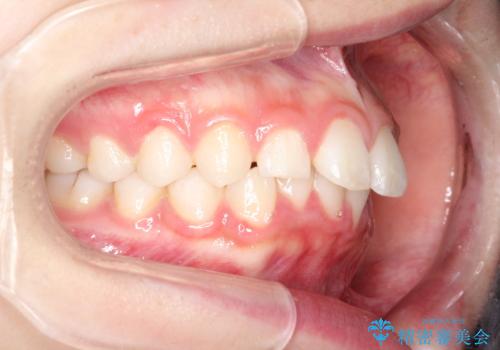

【インビザライン】出っ歯を引っ込めたい。

- 前歯の隙間と、出っ歯に見えることを主訴に来院されました。

できるだけ目立たない装置をご希望されましたので、インビザラインにて治療を行いました。

治療中は、できるだけ前歯を下げることができるように”顎間ゴム”を使用します。

”顎間ゴム”を利用することで、奥歯を後ろに動かす力を強めることができます。